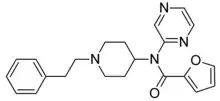

Anilidopiperidines

- 3-Allylfentanyl

- 3-Methylfentanyl

- 3-Methylthiofentanyl

- 4-Phenylfentanyl

- Alfentanil

- α-Methylacetylfentanyl

- α-Methylfentanyl

- α-Methylthiofentanyl

- Benzylfentanyl

- β-hydroxyfentanyl

- β-hydroxythiofentanyl

- β-Methylfentanyl

- Brifentanil

- Butyrfentanyl

- Carfentanil

- Fentanyl

- Lofentanil

- N-Methylcarfentanil

- Mirfentanil

- Ocfentanil

- Ohmefentanyl

- Parafluorofentanyl

- Phenaridine

- R-30490

- Remifentanil

- Sufentanil

- Thenylfentanyl

- Thiofentanyl

- Trefentanil

Structures